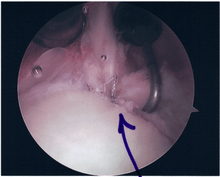

Surgical treatment of SLAP tears has become more common in recent years. The success rate for repairing isolated SLAP tears is reported between 74-94%.[8] While surgery can be performed as a traditional open procedure, an arthroscopic technique[9] is currently favored being less intrusive with low chance of iatrogenic infection.[10]

Procedure

Following inspection and determination of the extent of injury, the basic labrum repair is as follows.

- The glenoid and labrum are roughened to increase contact surface area and promote re-growth.

- Locations for the bone anchors are selected based on number and severity of tear. A severe tear involving both SLAP and Bankart lesions may require seven anchors. Simple tears may only require one.

- The glenoid is drilled for the anchor implantation.

- Anchors are inserted in the glenoid.

- The suture component of the implant is tied through the labrum and knotted such that the labrum is in tight contact with the glenoid surface.